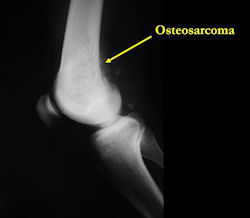

Conventional osteosarcomas are permeative lesions on plain radiographs (borders of the lesion cannot be clearly delineated)

- Most (90%) arise from the metaphysis of the bone

- Rarely (10%) arise from the diaphysis

Xray (plain radiographs) of the extremity

There are 3 radiographic presentations for osteosarcomas, depending upon the amount of osteoid/ossification and calcium deposition:

- Mixed sclerotic and lytic, permeative lesion most common radiographic presentation